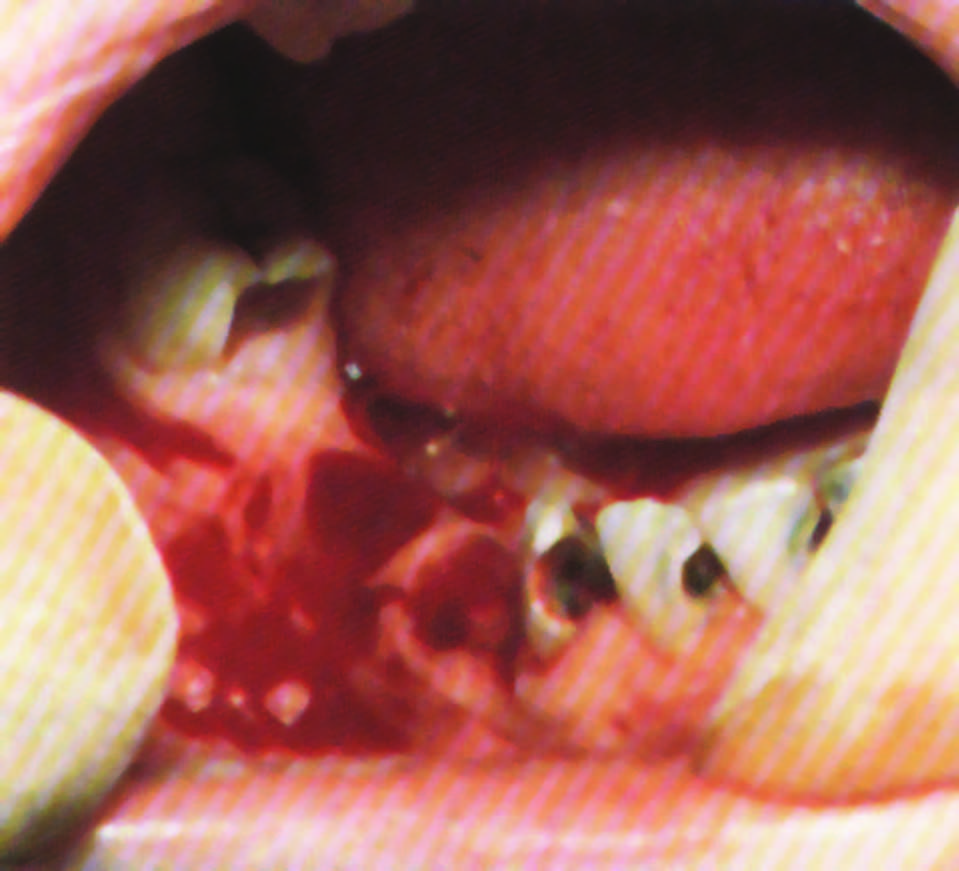

قد يحدث النزيف منذ مرحلة الوليد، فقد يحدث النزف بعد الختان لكن غالباً ما تبرز الأعراض عندما يبدأ الطفل بالحبو والمشي، حيث يلاحظ لديه سهولة التكدم (تشكل بقع زرقاء مكان الرضوض) وحدوث النزف في العضلات والمفاصل ويلاحظ عند هؤلاء الأطفال أن جرحاً صغيراً في الفم مثلاً قد يسبب نزفاً يستمر ساعات وأحياناً أياماً.

النزف المفصلي خاصة في مفصل الكاحل والركبة والمرفق وهذا النزف قد يؤدي إلى مضاعفات شديدة (مثل تلف المفصل) إن لم يعالج.